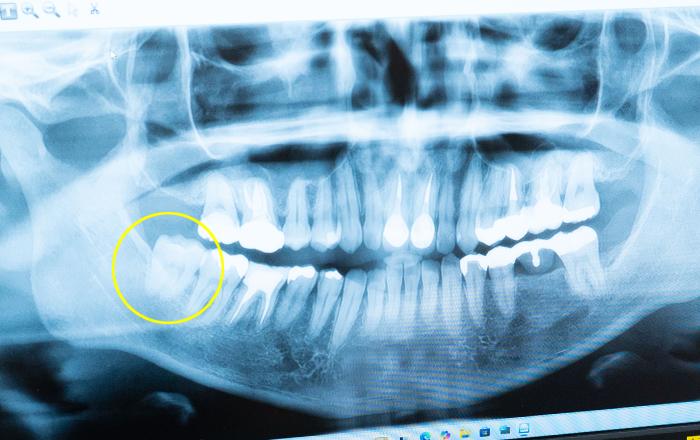

親知らずとは、永久歯の中で最も奥に位置し、前歯から数えて8番目に生えてくる歯のことを指します。通常、上下左右合わせて4本ありますが、人によっては生えてこない場合や、一部だけ生えることもあります。

この歯は「智歯(ちし)」や「第三大臼歯(だいさんだいきゅうし)」と呼ばれ、10代後半から20代前半に生えるのが一般的です。昔の人は、この歯が生える頃には親の手を離れていることが多かったため、「親知らず」と名付けたとされています。